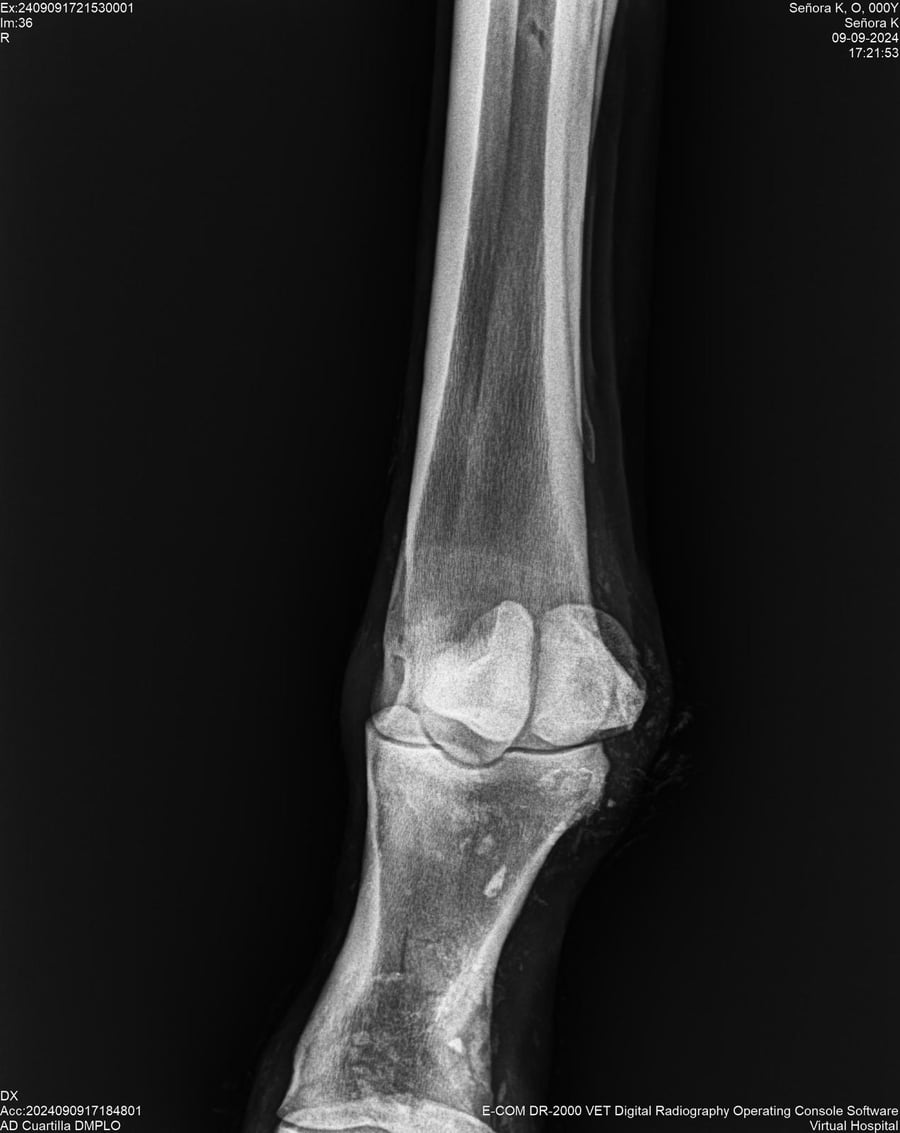

LOTE 44, SEÑORA K

Identificador: #291147-

Generacion 2022